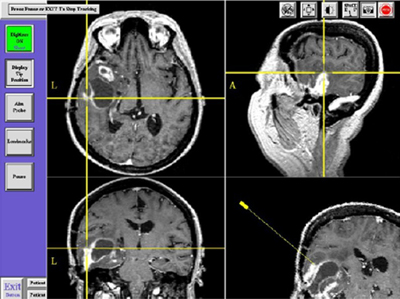

本世纪八十年代后期,神经外科医师、影像学专家和计算机学者通过多学科交叉合作,成功设计并研发了“神经外科显微手术导航系统”(Neurosurgical Microscopic Navigation System)。该系统应用计算机图形图像技术处理放射影像学(CT、MR、DSA、PET等)资料,重建二维或三维医学图像模型,帮助手术医生在术前、术中进行手术操作虚拟演示,规划手术入路,突破了现有手术器械和辅助设备的制约,帮助术者完成针对深部神经组织的一系列复杂而精细的操作,将病变周围正常神经血管结构的不必要损伤减少到最低程度。

电磁导航为最新研发的第三代导航系统,相对于以往光学导航系统体积庞大、设备笨重、视觉阻挡等不利因素,电磁导航的优势集中在:1)体积小巧,移动方便,有便携性:这一特性大大缓解了手术室空间不足的局面,利于各手术室设备共用;2)无视觉阻挡:导航工作所需空间较少,不需要抬升或移动显微镜等其他设备,一定程度上可以说“感觉不到导航的存在”;3)不需要参考环:电磁导航由于设计理念进步,降低系统性影像漂移的发生率,误差较小;4)导航精确平均影像匹配误差仅1.54mm:精确性较前大大提高;5)设备兼容性良好:其直流磁场范围仅覆盖术野周围,不影响术中应用的其他设备的正常使用。